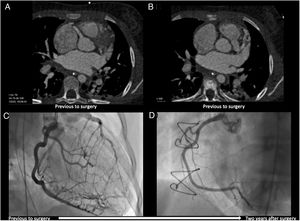

A 10-year-old girl, who has no relevant medical history, experienced, while running, cardiac arrest with shockable rhythm (ventricular fibrillation), recovering spontaneous circulation after one use of electrical defibrillation. The admission transthoracic echocardiogram reported normal biventricular function and unidentifiable left coronary artery ostium. The computed tomography angiography and coronary angiogram revealed a huge right coronary artery, an anomalous origin of left coronary artery (LCA) from the main pulmonary artery (Figure 1A–C) and confirmed the rare diagnosis of anomalous LCA from the pulmonary artery (ALCAPA) syndrome. The patient underwent successful heart surgery with direct reimplantation of the proximal LCA in the aortic root. Two years later, she remained asymptomatic with normal biventricular function on serial transthoracic echocardiograms. The patient performed a treadmill stress test (Bruce protocol) which revealed normal functional capacity (11 metabolic equivalent) and was clinically negative but electrically positive for myocardial ischemia. She underwent a coronary angiogram which showed no pathological narrowing of the reimplanted LCA. Additionally, it was noted that both coronary arteries presented normal dimensions (Figure 1D).

In summary, the authors present a rare case of ALCAPA syndrome with uncommon and late presentation, successfully treated with cardiac surgery and with an impressive reshaping of coronary dimensions during follow-up.